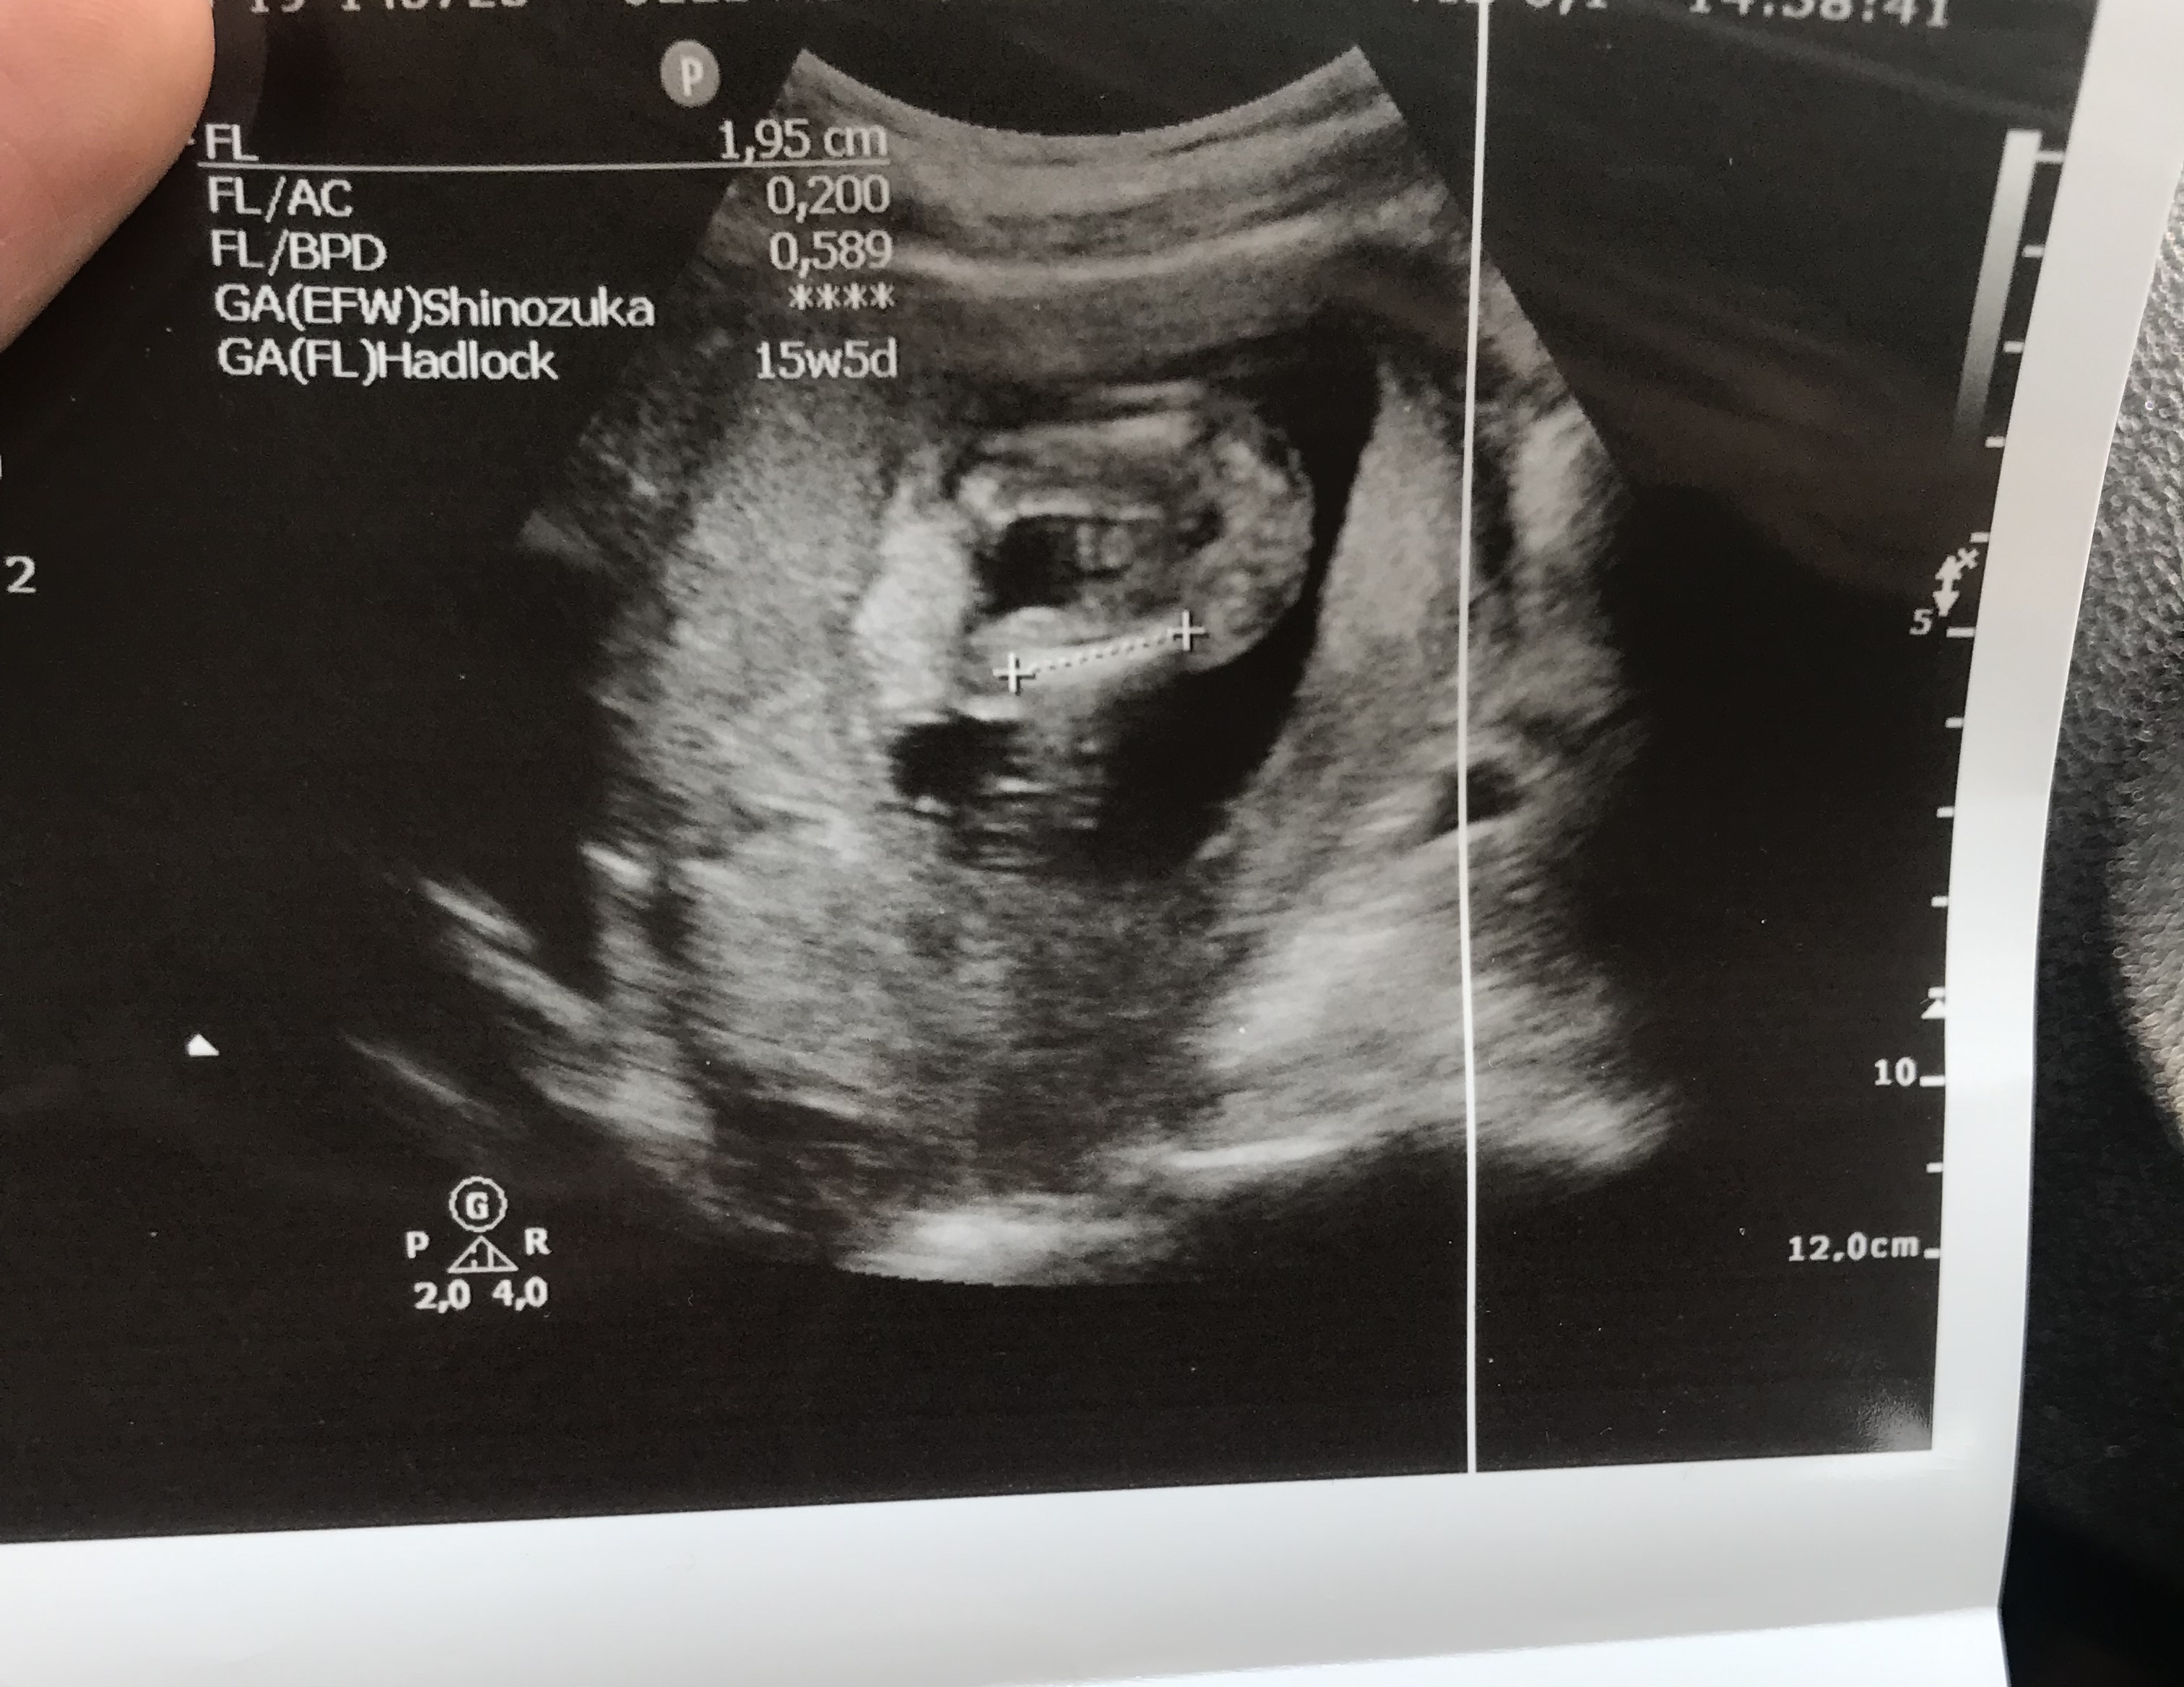

Benm kendi doktorum olmadğı içn 12. hftada farklı bir doktora ikili test yaptrmştm ve cinsiyetinin kız olduğunu söylemşti

ama 16. haftada tekrar gittiğimde kendi doktorum erkek olduğunu söyledi sizce nedir? doğru sonuç için detaylıyı mı beklemeliyim???

Belittiğiniz haftalarda cinsiyet tahmininde yanılmalar olabilir. Gebeliğin 17-18-20 . haftalarında bebeğinizin cinsiyetini net olarak öğrenebilirsiniz.